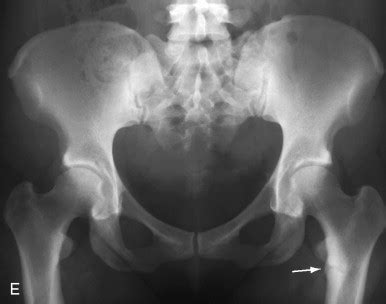

Alright folks, let’s get down to the nitty-gritty of what we actually see on those X-rays when we suspect osteomalacia . The star of the show, the one finding that most people associate with osteomalacia, is undoubtedly the Looser zone . These guys are also known as pseudofractures or Milkman’s lines, and they are absolutely key. Imagine a thin, horizontal lucent line crossing the bone, usually perpendicular to the cortex. They’re not true fractures in the sense of a complete break, but rather areas of incomplete healing or unmineralized osteoid. The most common locations for Looser zones are the inner aspect of the femoral neck, the pubic rami, the ribs, the scapulae, and the shafts of long bones. When you see these, especially multiple ones, it’s a pretty strong indicator that something is up with bone mineralization. It’s like finding a series of tiny, horizontal cracks in a piece of pottery. Remember, these are not through-and-through fractures; they are often quite subtle and can be easily missed if you’re not specifically looking for them. The bone on either side of the Looser zone might appear sclerotic (denser), which can make the lucent line stand out more. Another significant radiographic finding is generalized osteopenia . This means the bones, overall, appear less dense than they should be. On an X-ray, this translates to the bones looking more gray and less white. The trabecular pattern within the bone might also become less distinct and more coarsened, losing its fine, intricate mesh-like appearance. Think of it like the intricate lace of a healthy bone becoming a more blurry, chunky pattern. We also need to be vigilant for fractures . In osteomalacia, patients are prone to insufficiency fractures , which are fractures that occur with minimal or no trauma due to the weakened state of the bone. These can occur in various locations, including the spine (vertebral compression fractures), pelvis, and long bones. These fractures might not always have the typical sharp, clean edges of acute fractures; they can sometimes appear more ill-defined or sclerotic. The cortical bone , the smooth outer shell of the bone, can also be affected. It might appear thinned and indistinct, with loss of its sharp, clear outline. In some cases, the ends of the long bones might appear widened or flared due to the accumulation of unmineralized osteoid. The overall appearance of the bone can sometimes be described as “mottled” or “chalky” . It’s crucial to differentiate these findings from other conditions that can cause osteopenia or fractures, such as osteoporosis, hyperparathyroidism, or metastatic disease. This is where our knowledge of typical distributions and appearances comes into play. By carefully analyzing these classic radiographic findings – Looser zones, osteopenia, fractures, and changes in cortical and trabecular bone – we can confidently diagnose osteomalacia radiology and guide the appropriate management for our patients.

So, we’ve done our detective work, identified the signs of osteomalacia radiology on the images, and helped make the diagnosis. What happens next for the patient, and how does radiology continue to play a role? Well, guys, the management of osteomalacia is multifaceted and hinges on addressing the underlying cause, correcting the biochemical abnormalities, and preventing fractures. Once the diagnosis is confirmed, the primary goal is to replete the deficient nutrients, usually vitamin D and calcium. This often involves high-dose vitamin D supplementation, sometimes with active forms like calcitriol, depending on the specific etiology and the patient’s kidney function. Phosphate levels also need to be monitored and corrected if deficient. Radiology’s role doesn’t stop after the initial diagnosis. Follow-up imaging is often crucial to monitor the effectiveness of treatment. We’ll typically be looking to see if those pesky Looser zones are healing. Healing often appears as a gradual sclerosis (thickening and increased density) along the margins of the pseudofracture, with the lucent line becoming less conspicuous and eventually disappearing. The overall bone density may also show improvement over time, though this can be a slower process. We might also use follow-up X-rays to check for the development of new fractures or to assess the stability of existing ones. If a patient has had a fracture, subsequent imaging will be important to ensure proper healing and to rule out complications. In cases where the etiology is related to malabsorption, follow-up imaging might also be used to monitor the underlying gastrointestinal condition. For instance, if celiac disease is the culprit, serial imaging might be used to assess the healing of the small bowel mucosa or to monitor for complications. Quantitative imaging techniques , like QCT, are becoming increasingly valuable in follow-up. They allow for objective measurement of bone mineral density changes, providing a more precise assessment of treatment efficacy than subjective visual assessment alone. This can be particularly helpful in determining when treatment can be scaled back or stopped. Patient education is also a vital component, and radiology can play a part here too. Showing patients their own X-rays, pointing out the Looser zones before and after treatment, can be a powerful visual aid to help them understand their condition and the importance of adherence to therapy. It reinforces the impact of the disease and the benefits of treatment. Ultimately, the effective management of osteomalacia relies on a strong collaboration between the clinician, the patient, and the radiologist. Our role in osteomalacia radiology is to provide accurate initial diagnoses, monitor treatment response through serial imaging, and help prevent debilitating fractures, ensuring the best possible outcomes for our patients. It’s a continuous process, and radiology is there every step of the way.